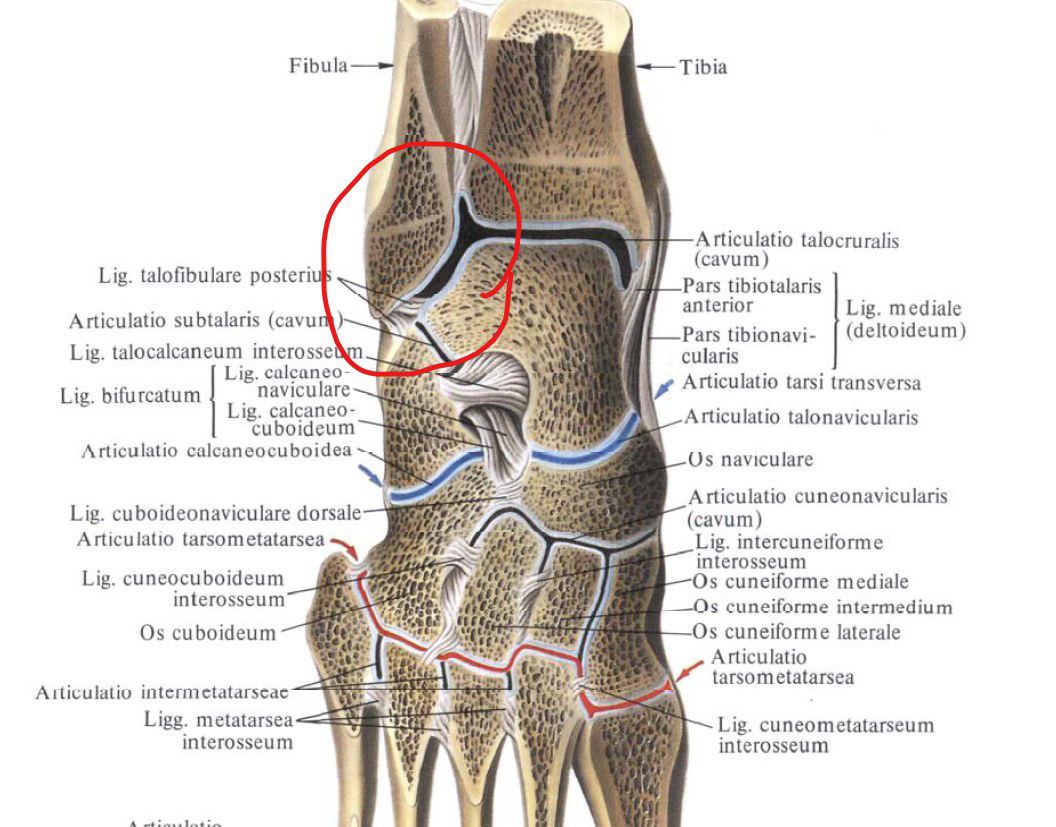

Анатомия голеностопа: Сухожилия и их строение